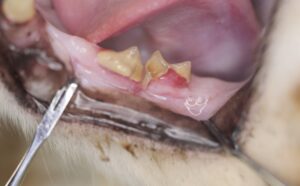

Sometimes the only sign is a small red area at the gumline, called a “resorptive lesion.”

How Is Tooth Resorption Diagnosed?A thorough oral examination under anesthesia is the best way to diagnose tooth resorption.At Animal Medical of New City, diagnosis includes:

- Complete oral exam

- Dental X-rays (radiographs) to evaluate the roots and structures below the gumline

- Identification of affected teeth and the extent of disease